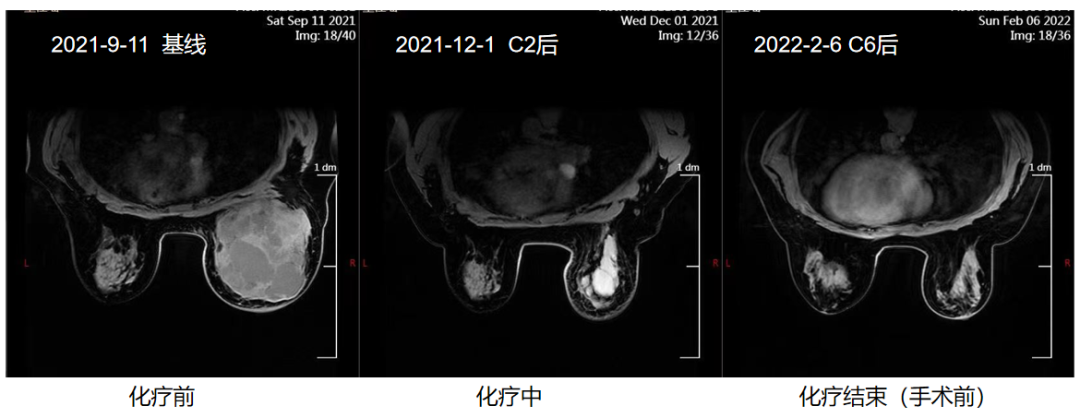

GeparSixto等多项研究结果表明[2-4],HRD可用于早期三阴性乳腺癌患者含铂新辅助化疗疗效预测,在接受含铂方案新辅助化疗的三阴性乳腺癌患者中,HRD阳性人群可获得显著较高的病理完全缓解(pCR)率。依据NGS检测结果,临床将患者新辅助治疗方案调整为TP方案(顺铂+贝伐珠单抗+白蛋白紫杉醇)。患者于2021年9月至2022年2月期间完成6周期治疗,治疗期间肿瘤标志物CA125、CA153持续下降(图3),肿块明显消退(图4)。完成新辅助治疗时,疗效评价为部分缓解(PR)。

图4. 6周期含铂新辅助化疗疗效评价:肿块明显消退